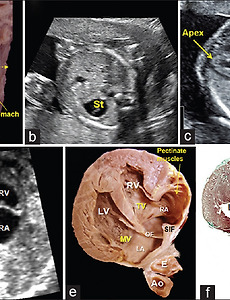

thorax and abdomen of a 20-week human fetus The thorax and abdomen of a 20-week human fetus dissected to show the orientation of the heart in relation to the remaining organs (liver, stomach). The echocardiographic first plane (yellow-dotted line) starting just below the level of the diaphragm. (b) Abdominal echocardiographic view showing the fetal stomach to the left. (c) View of the apex pointing to the left. (d-f) A composite of echoca.. 2020. 5. 3. 이전 1 다음